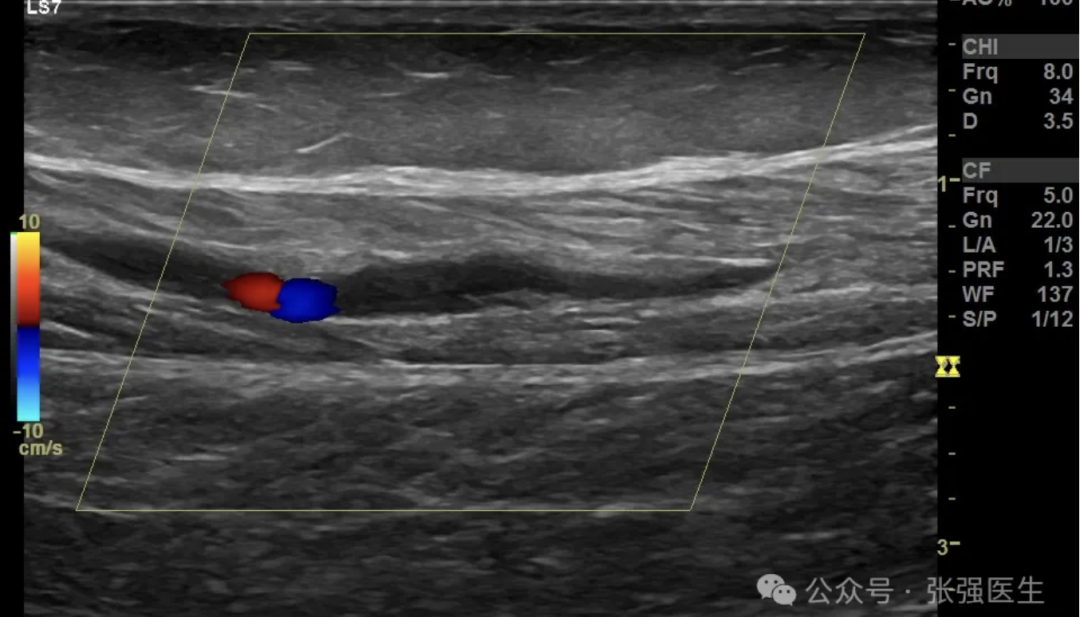

近几年,体检或彩超报告上常常会出现这样一行字:“肌间静脉可见血栓形成。”

其实,大多数情况下,这是一种被“过度紧张”的血栓。医学上称为 肌间静脉血栓(calf muscle vein thrombosis,CMVT),属于血管系统中最温和、最容易恢复的一类。

肌间静脉血栓指的是在这些小静脉支内形成的局部血块。它往往发生在感冒、久坐、外伤之后。多数血栓体积小、流速慢、局限性强,并不会脱落到肺部,也不会危及生命。